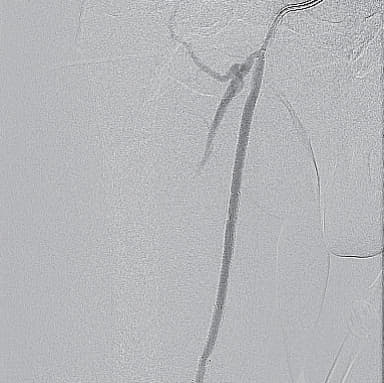

- 4 Fr IMA(内胸動脈用)造影カテーテル併用し0.014 inch wireを閉塞内へ進入し、ステント近位まで比較的容易にワイヤリングすることに成功(血管内超音波(IVUS)にてintra-plaqueであることを確認)

- ステント近位端は非常に硬化しており、0.014 inch wireでのknuckle wiringおよび0.035 inch wire のtail 側でもステント内へ進入できず

- 4 Fr IMA造影カテーテルにマイクロカテーテル併用下でtapered coil typeの0.018 inch wireにてなんとかステント近位端を通過(図2)